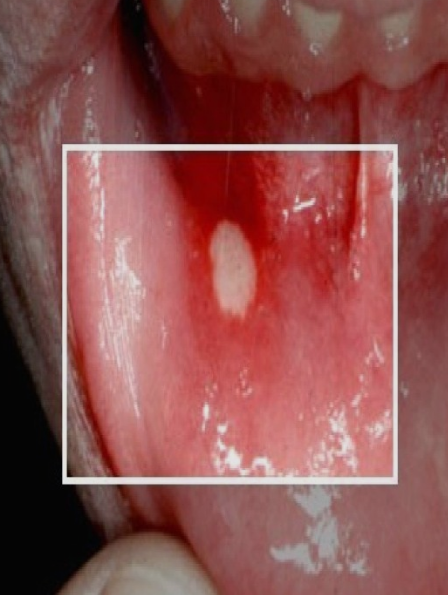

1. 구강 궤양

구강궤양은 혀를 포함하여 입안의 어느 부위에서든 발생할 수 있는데 보통 원형으로 파인 형태이며 하얗게 덮여 있습니다. 궤양이 있는 부위는 매우 아파서 식사를 하기가 힘들 정도인 경우도 있고 대개 1~2주 내에 아무 흔적 없이 깨끗이 낫지만 시간이 지나면 궤양이 다시 재발합니다.